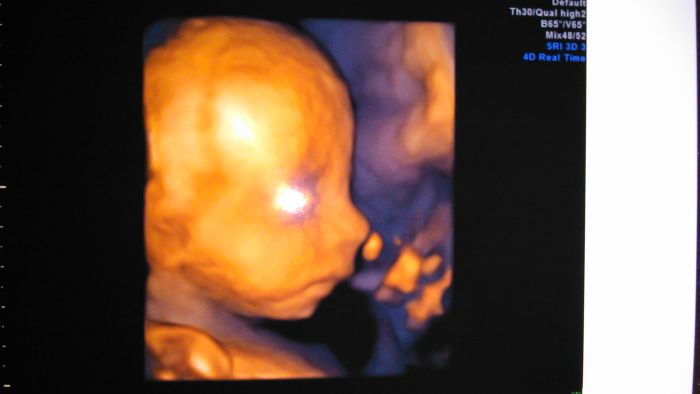

Tak jsme zpátky z 3D UTZ. Potvrdili nám tu holčičku,tak jsem ráda. :-) Je stejná jak naše Marunka. :-)